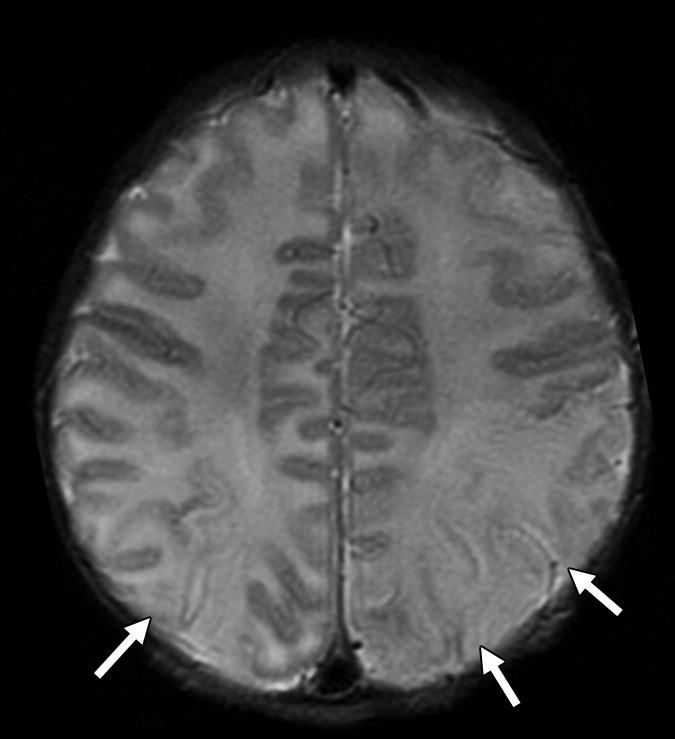

(В) МР-скан головного мозга определяет множественные гиперинтенсивные области в обеих гемисферах, в основном локализованные в белом и на границе серого и белого вещества (стрелки).

(С) При использовании последовательности DWI определяются участи ограничения диффузии (что отвечает ишемии) в таламусе, гипотоламусах и задней части внутренней капсулы справа (стрелка). Неделю спустя у пациента развилась картина гемиплегии.

Рисунок 1 | Асимметричные области патологически повышенного МР сигнала в медиальных отделах обеих височных долей, больше выраженные в корковом веществе

Рисунок 2 | В последовательности DWI у того же пациента определяются области повышения сигнала в обоих лобно-височных областях. ИДК подтвердила ограничение диффузии